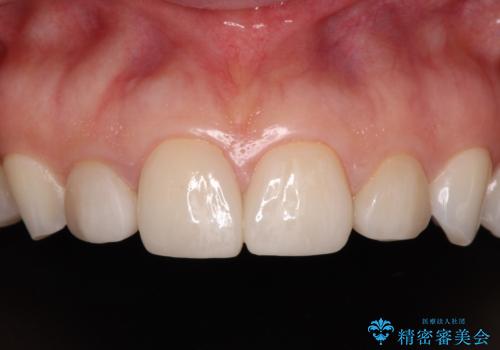

- 大きすぎる上顎前歯と、隙間の空いた下顎歯列を気にして来院された患者様です。

上顎前歯にはセラミッククラウンが装着されており、顔や他の歯と比較して幅の大きい状態でした。

下顎前歯は空隙歯列弓であったので、アンカースクリューとワイヤー装置を用いてスペースを閉じていくこととし、上顎前歯は矯正治療用の仮歯に置き換えた上で、仮歯の大きさを削って小さくしながら、上下前歯部の部分矯正を行うこととしました。

矯正治療後は、仮歯とした上顎前歯をオールセラミッククラウンにて補綴治療を行うこととしました。

日本と海外を拠点に仕事をされていらっしゃるため、数ヶ月治療があいてしまうことがあり、期間はかかりましたが、2年間で望み通りの前歯に仕上げることができました。